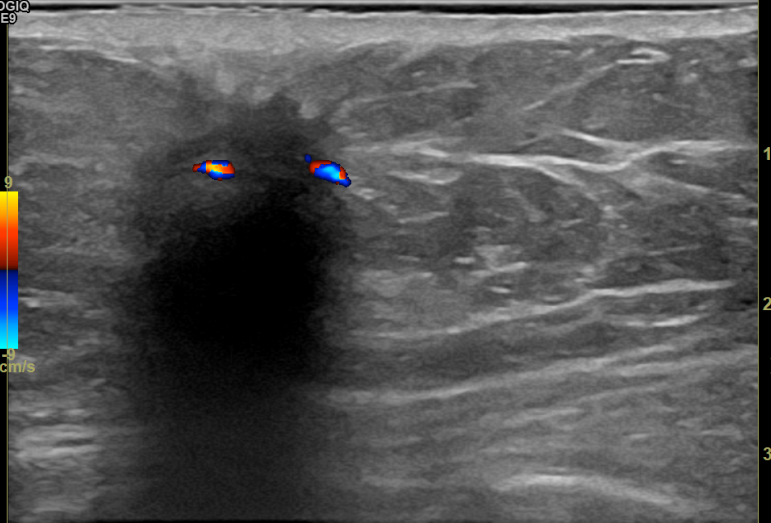

상기환자 외부검사이상으로 조직검사위해 내원하신 60대 중반 여성분으로

우측혹 조직검사 시행해 침윤성암으로 진단되었습니다